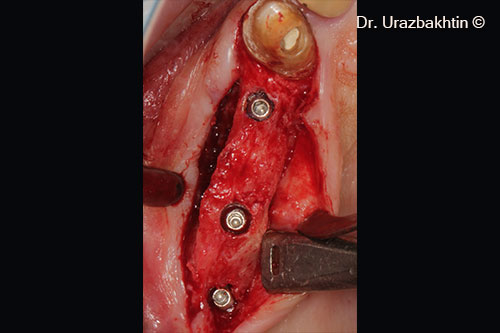

Tăng chiều cao xương hàm bằng kỹ thuật cắt xương ngang vùng hàm

Một bệnh nhân nam (77 tuổi) cần phẫu thuật nâng cao chiều dọc xương hàm.